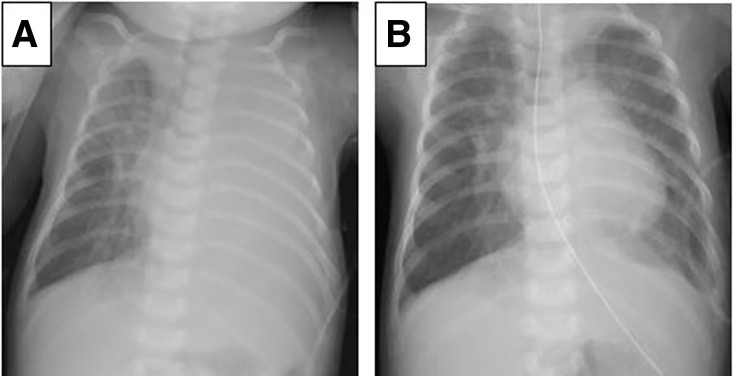

Case presentation: The patient with complete atrioventricular septal defect, patent ductus arteriosus, pulmonary hypertension, and chromosomal abnormality with trisomy 21 underwent pulmonary artery banding and patent ductus arteriosus ligation through median sternotomy. The postoperative course was complicated with chylothorax; conservative treatment was not effective, so surgical treatment was selected. Indocyanine green was injected subcutaneously between the first and second toes on the left side 30 min before surgery to identify the site of leakage. We could detect the lymphatic leakage from the para-aortic lymph node by indocyanine green camera in the left thoracic cavity, and the leakage sites could be closed with interrupted sutures.